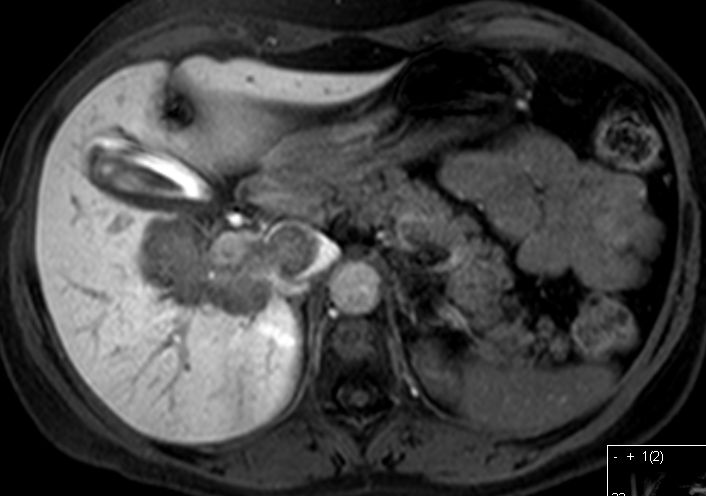

| Lebermetastasen | 51-jährige Patientin mit metastasiertem

Mammakarzinom. Leber vergrößert und von Metastasen durchsetzt.![]() |